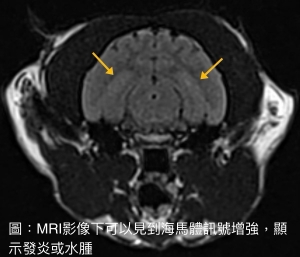

- MRI 成像:可見海馬區域出現高訊號或體積萎縮;MRI同時也能排除腫瘤等其他病因 (圖3)